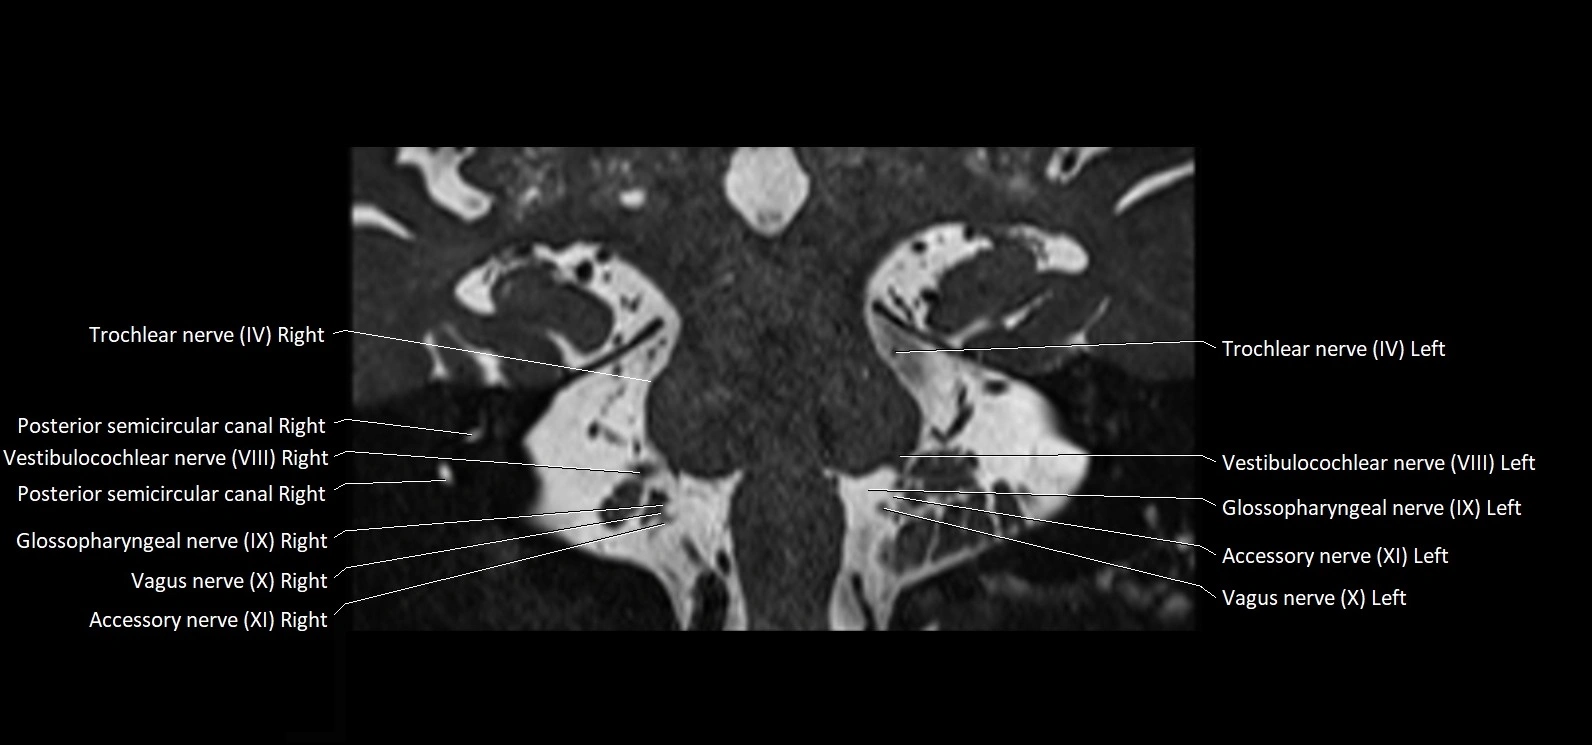

MRI images

image